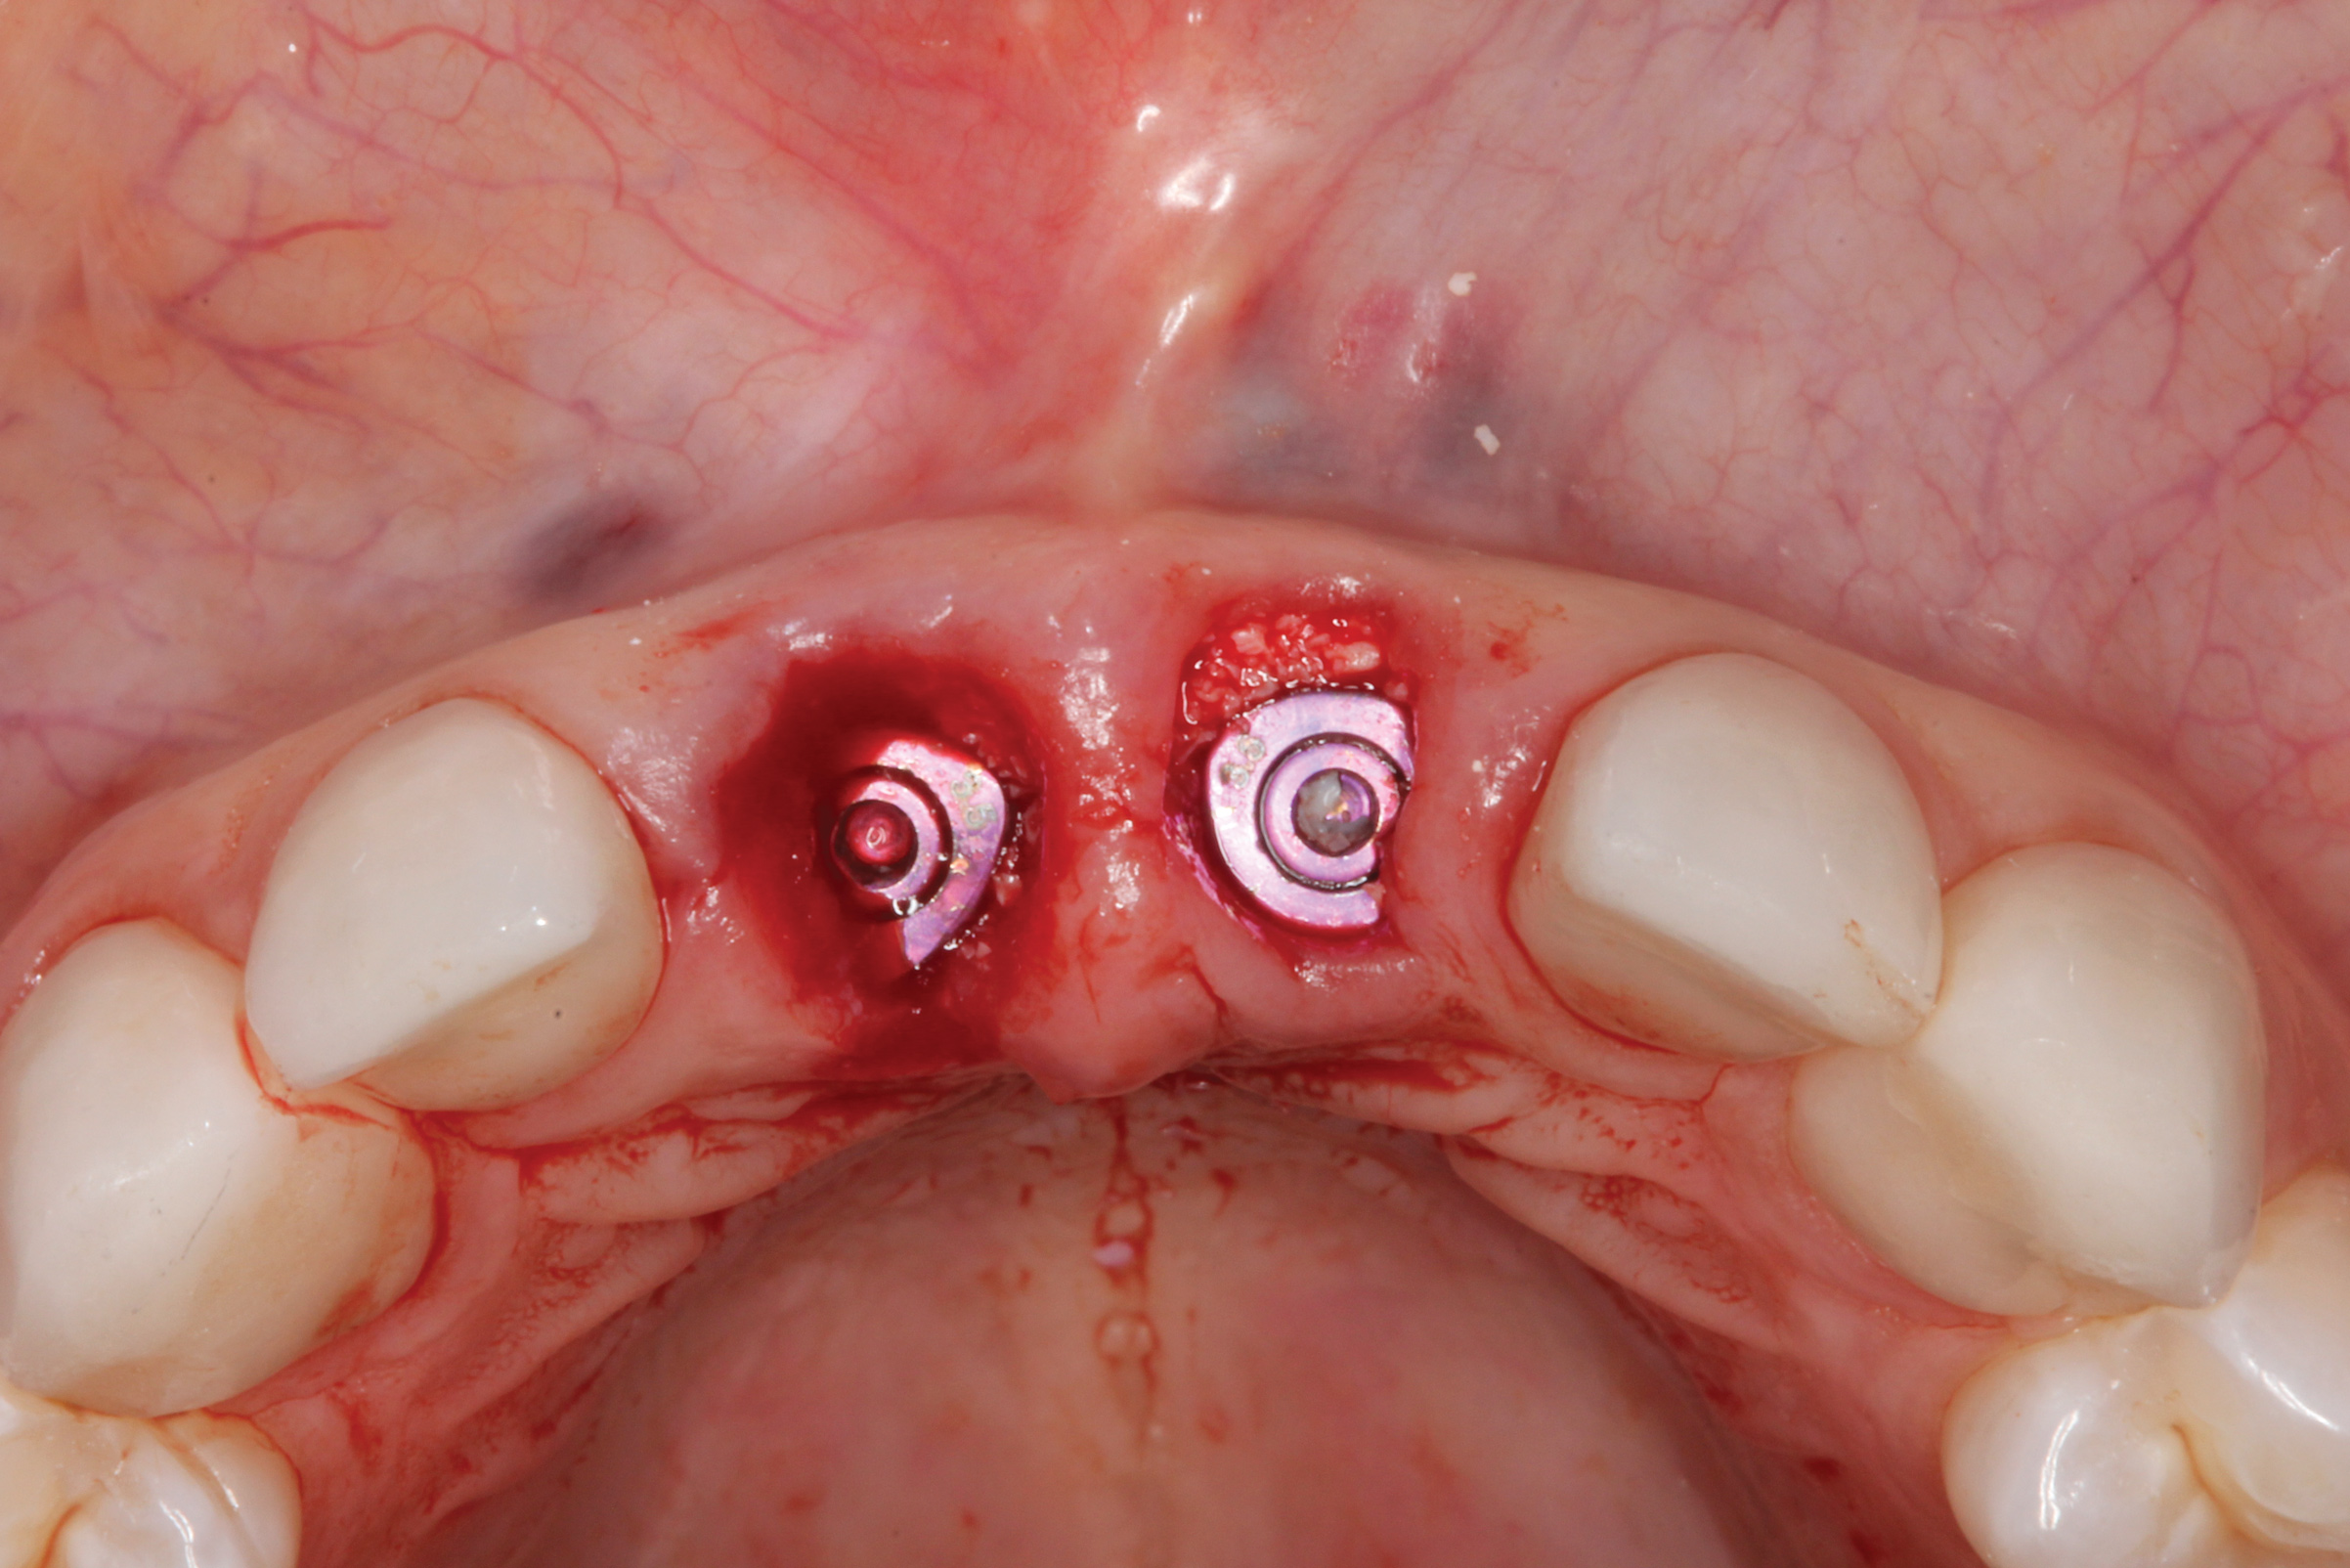

The surgery was performed under local-regional anesthesia. The thermoplastic retainer was placed over the remaining teeth and its fit/stability verified. Atraumatic extractions of teeth Nos. 8 and 9 were performed, and intact buccal bone was verified. Osteotomy site preparation and immediate implant placement were performed using the dynamic surgical navigation system. Two 3.6 mm x 9 mm implant fixtures (Astra Tech EV, Dentsply Sirona, dentsplysirona.com) were placed. SmartPegs (Osstell, osstell.com) were attached to the implants to show the trajectory of the fixture positioning. After implant placement, anorganic bovine bone matrix (Bio-Oss®, Geistlich Pharma, geistlich-na.com) was used to graft the implant alveolus "gap," and healing abutments were placed (Figure 9 and Figure 10). The patient was provided with an interim removable appliance for tooth replacement.

Fig 9. Dynamic surgical navigation, demonstrating flapless immediate implant placement. “Smart pegs” were placed to show the trajectory of the fixture positioning.

Figure 9

Fig 10. Healing abutments were placed, and implant/alveoli gaps were managed with placement of anorganic bovine bone.

Figure 10